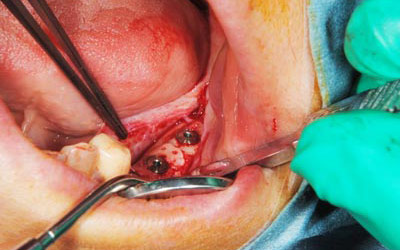

骨の移植手術後、移植した骨片が生着するのを数か月待って、インプラント埋入手術を行いました。写真はその時のもので、移植した骨が周囲の骨と一体化して、しっかりと骨が増えているのが分かります。

インプラントを埋入した時の写真です。